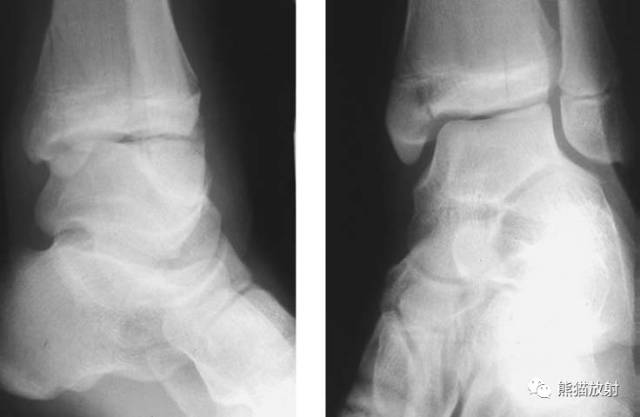

Salter-Harris II型:骨折累及骺板及干骺端,骨骺骨折中最多见(75%),预后较差。

第二型(Ⅱ型) 骨骺分离伴干骺端骨折。该型损伤最多见,占骨骺损伤的48.2%,好发部位在桡骨远端、肱骨近端及胫骨远端。多发生在10一16岁的儿童,骨折线通过肥大并累及干骺端的一部分,骨折片呈三角形,在骨折端成角之凸侧有骨膜撕裂,而凹侧骨膜完整、复位容易,预后良好。

第三型(Ⅲ型) 骨骺骨折。属于关节内骨折,骨折线从关节面开始穿过骨骺,再平行横越部分骺板的肥大层。该型占骨骺损伤的4%。多发生在胫骨远端内侧或外侧和肱骨远端外侧。无移位关节面平整者预后良好,有移位者需切开复位内固定,—般移位超过2mm者既是切开复位内固定的适应证。

第四型(Ⅳ型) 骨骺和干骺端骨折。该型也较多见,仅次于第二型,占30.2%;骨折线呈斜形贯穿骨骺、骺板及干骺端,由于骨折线同过生长板全层,所以容易引起生长发育障碍和关节畸形,多见者为鱼尾状畸形。此型多见于10岁以下小儿的肱骨外髁及年龄较大儿童的胫骨远端,此型必须切开复位及内固定。